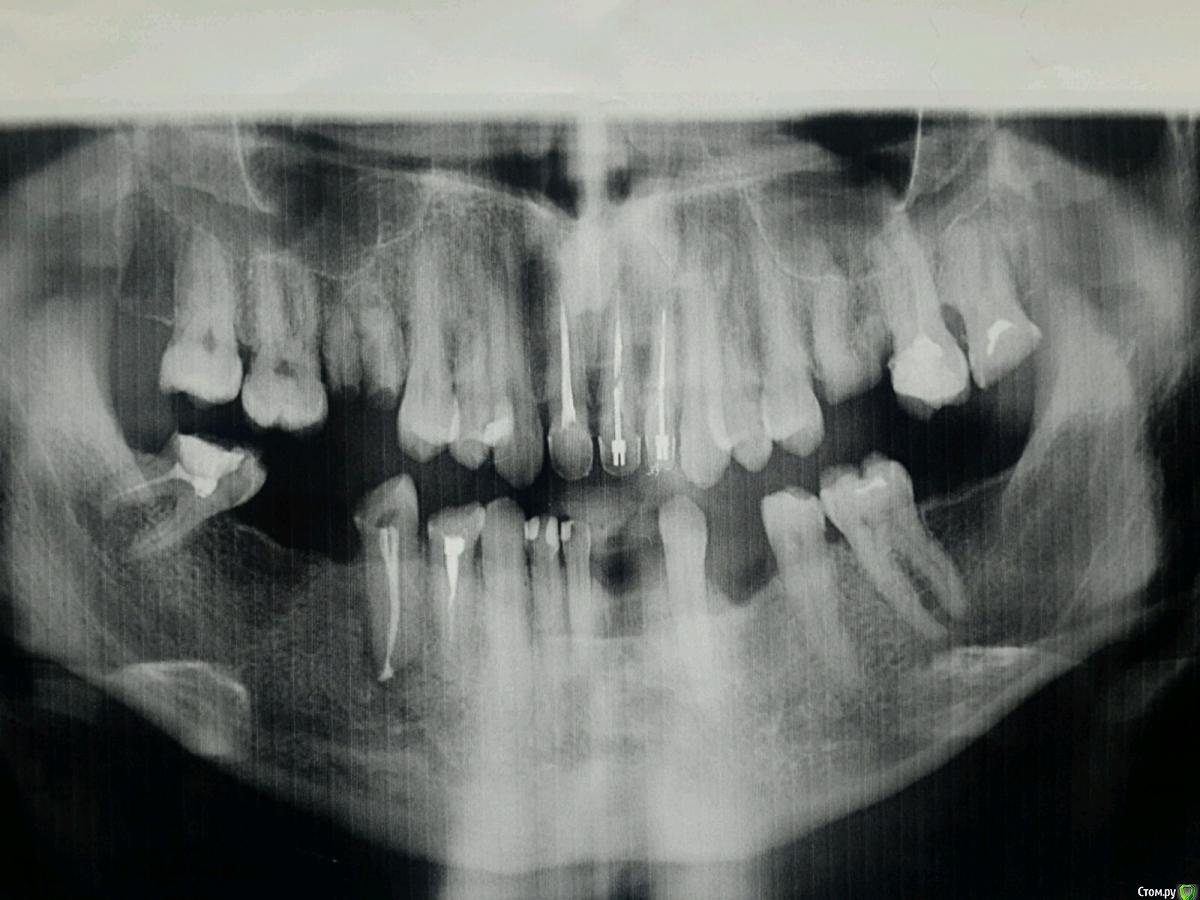

IvanK Опубликовано 27 сентября, 2015 Поделиться Опубликовано 27 сентября, 2015 Консультация ортопеда и ортодонтаудаление 16, 26,28, 45?, 48... вариантов протезирования много: мостовидные конструкции, съемное протезирование, протезирование с опорой на имплантаты 1 Ссылка на комментарий

DIMTO Опубликовано 21 октября, 2015 Автор Поделиться Опубликовано 21 октября, 2015 Консультация ортопеда и ортодонтаудаление 16, 26,28, 45?, 48... вариантов протезирования много: мостовидные конструкции, съемное протезирование, протезирование с опорой на имплантатыСкажите пожалуйста имплантация в моем случае возможна и сколько нужно имплантатов?Или какой съемный протез в моем случае лучше? Ссылка на комментарий

IvanK Опубликовано 22 октября, 2015 Поделиться Опубликовано 22 октября, 2015 имплантация в моем случае возможна да сколько нужно имплантатов? необходима очная консультация у ортопеда и хирургу Или какой съемный протез в моем случае лучше? частичный съемный протез Ссылка на комментарий